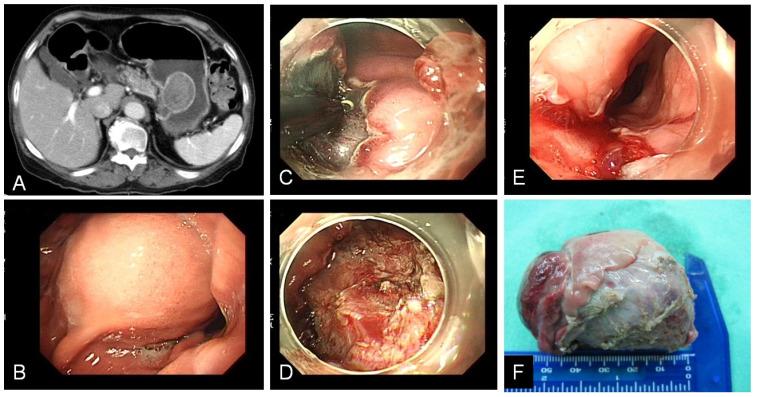

内镜下黏膜剥离术在胃黏膜肿瘤和胃上皮下肿瘤中的应用比较

Comparison of Endoscopic Submucosal Dissection Application on Mucosal Tumor and Subepithelial Tumor in stomach.

Endoscopic submucosal dissection is minimal invasive endoscopic procedure to deal with gastric tumor. Initially, it was developed to resect mucosal neoplasm since 2000 and extended its application to submucosal tumor in the following years. Although the basic ESD skills are similar in gastric mucosal tumor and subepithelial tumor, the success rate, complication may be different between the two types of gastric tumor resection. This retrospective study is conducted to analyze the ESD procedure in gastric mucosal tumor and subepithelial tumor. From 2007 to 2016, we reviewed all patients who underwent endoscopic submucosal dissection for gastric mucosal tumor and subepithelial tumor in Kaohsiung Medical University Hospital. Totally, 35 patients with gastric subepithelial tumor and 41 patients with gastric mucosal tumor received endoscopic submucosal dissection are enrolled. Among 35 patients with subepithelial tumor, 32 (91.4%) patients achieved curative treatment. 1 patient received emergent operation and 2 patients received salvage operation to complete tumor resection. 8 patients (22.9%) occurred perforation and no delay bleeding was found. Among 41 patients with mucosal neoplasm, 30 (71.4%) patients achieved curative treatment. 2 patients received emergent operation and 9 patients received salvage operation to complete tumor resection. 9 patients (21.9%) occurred complication, 6 patients occurred delay bleeding and 3 patients had perforation. Comparing ESD between gastric mucosal tumor and subepithelial tumor, ESD had similar efficiency in curative treatment. However, ESD in subepethelial tumor encountered higher perforation and lesser delay bleeding.

摘要